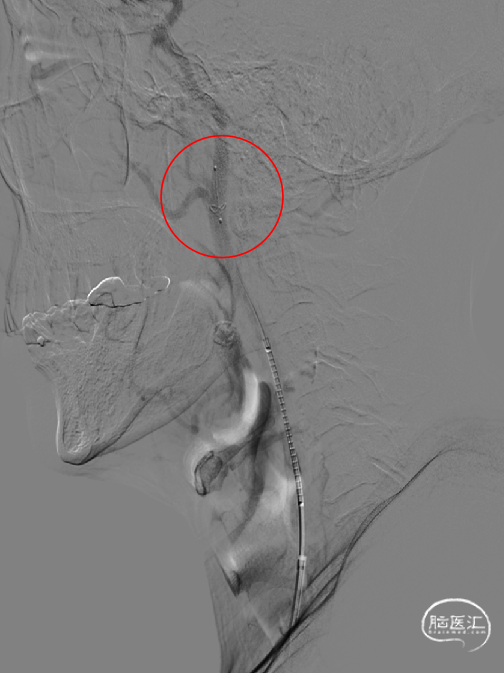

球囊预扩:

微导丝路图下通过右侧颈内动脉起始部狭窄处至C2段,沿微神途威龙导丝送入Safecer栓塞保护器路图下超选至右侧颈内动脉颈段远段,撤出微导丝,小心释放保护伞,延微导丝送入4.0*30mm球囊超选至右侧颈内动脉狭窄处,12atm快速充盈球囊及回抽,患者心率、血压未见变化,撤出球囊。